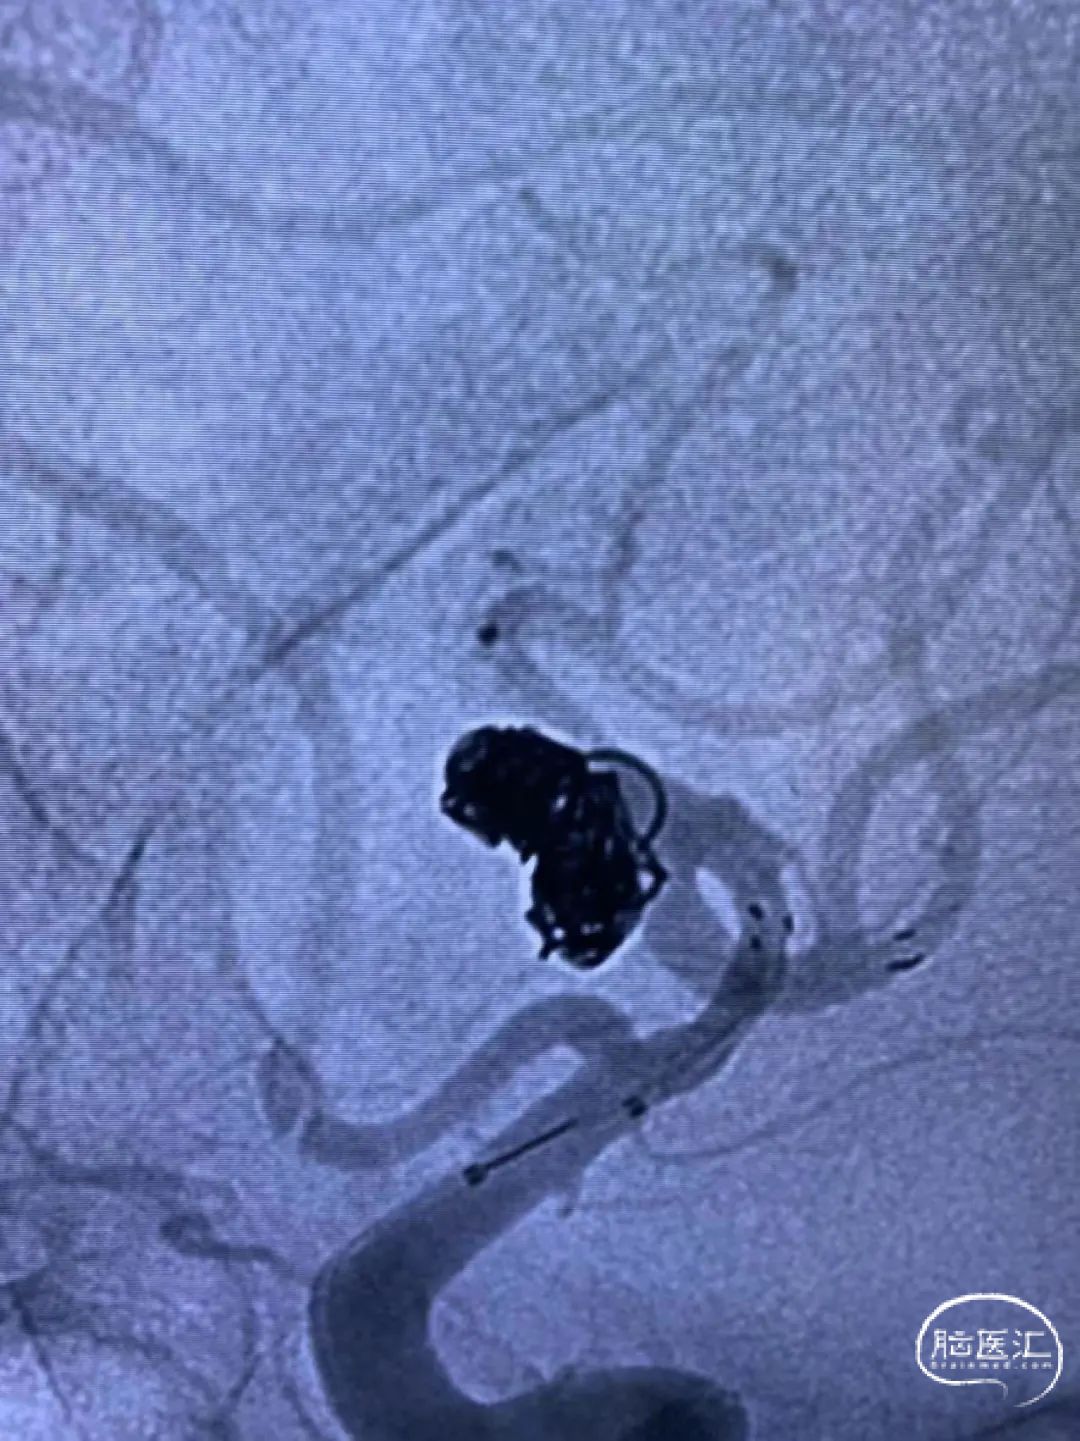

下图可以看出Atlas支架和弹簧圈位置良好,并完美展示出Atlas支架穹隆效应可以有效避免患者使用双支架,在降低费用的同时降低复杂手术操作带来的潜在风险。

Atlas支架穹隆效应,较好的保护了大脑中动脉上干和下干,避免了使用双支架(但有备无患,将支架导管穿网眼送入另外一条可能受影响的分支血管是很有必要的)。

术后情况

术后正侧位造影提示动脉瘤良好栓塞,载瘤动脉保护良好。